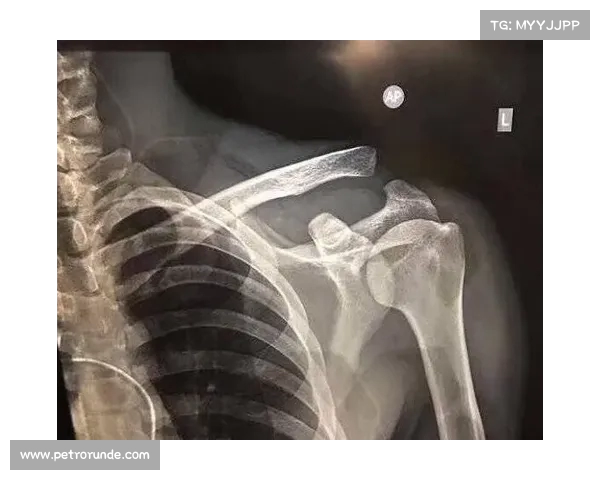

穆西亚拉的伤病源自一次比赛中的意外碰撞,导致其左腓骨发生骨折,并伴随韧带损伤。根据初步的医疗报告,左腓骨的骨折位置较为复杂,既涉及到骨头的断裂,又有可能影响到附近的韧带和关节组织。韧带的损伤使得该部位的稳定性大大降低,增加了康复的难度。根据医生的判断,这样的伤势需要通过手术进行修复,并且患者的恢复时间较长。

具体来说,腓骨的骨折通常是由于高强度的撞击或扭曲动作引起的,而穆西亚拉的伤情很可能与比赛中的激烈身体对抗密切相关。腓骨虽是下肢的辅助骨骼,但其在支撑与运动中扮演着重要角色,伤后恢复不仅需要时间,也需要极其专业的康复训练。与此同时,韧带损伤进一步增加了伤情的复杂性,因为韧带的恢复通常比骨骼更为缓慢。

从医生的角度来看,穆西亚拉的康复期预计将达到四至五个月。在此期间,除了进行必要的手术修复外,还需要严格的物理治疗和康复训练。这段时间对于穆西亚拉来说,是身体与心理的双重考验。